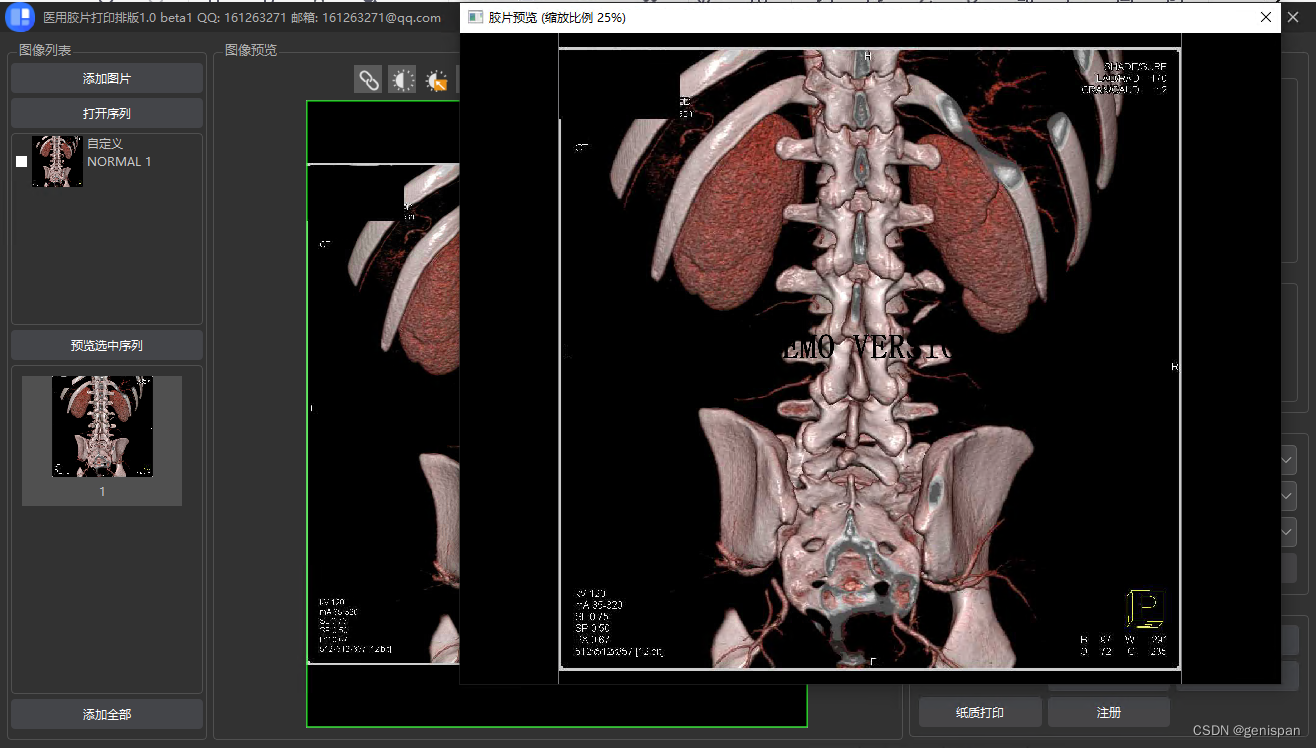

灰度图像打印:

彩色图像打印:

文章详细介绍了DICOM图像的两种打印类型——灰度图像和彩色图像,包括DICOM图像的关键元数据如像素信息、窗宽窗位等。在组建待打印的数据集时,涉及了如何设置各种参数。此外,还讨论了使用Qt库构建RGB图像数据的过程,以及图像对齐和分页打印的策略。最后展示了打印效果的预览。

文章详细介绍了DICOM图像的两种打印类型——灰度图像和彩色图像,包括DICOM图像的关键元数据如像素信息、窗宽窗位等。在组建待打印的数据集时,涉及了如何设置各种参数。此外,还讨论了使用Qt库构建RGB图像数据的过程,以及图像对齐和分页打印的策略。最后展示了打印效果的预览。